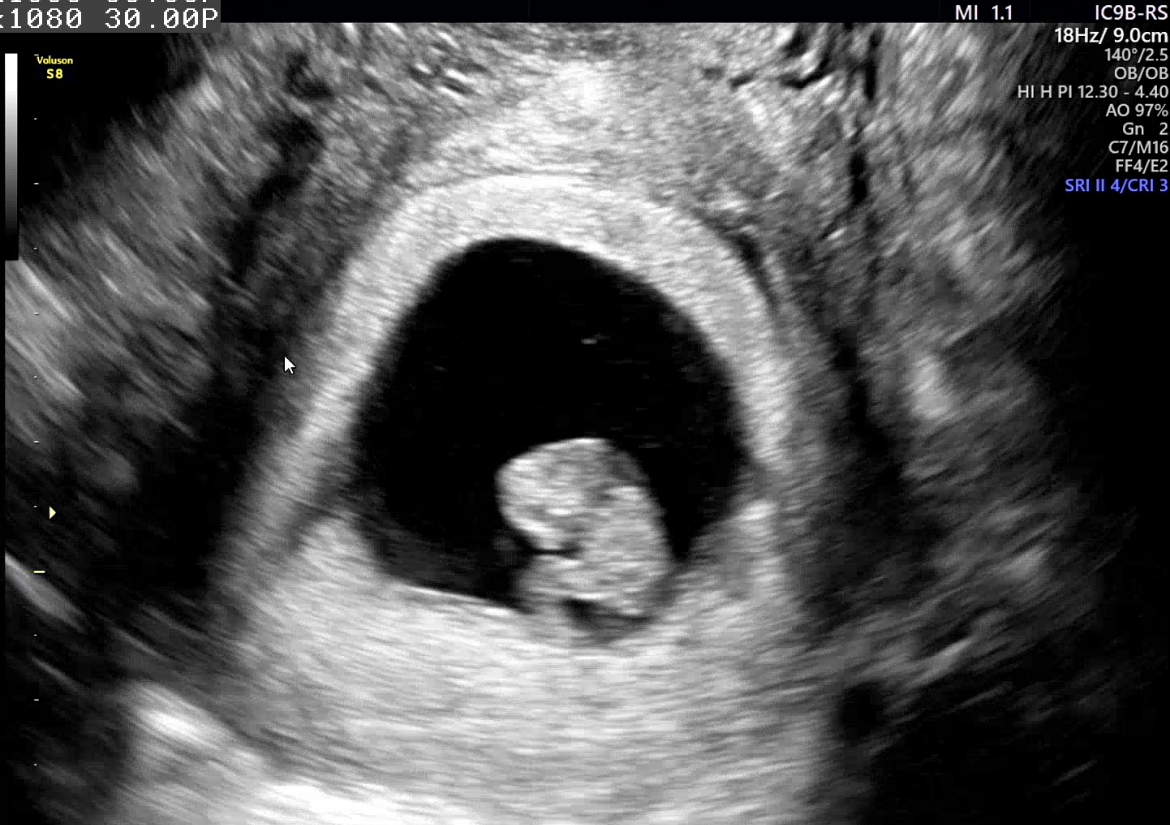

| 가슴 떨리는 임신 이야기를 공유해 주세요. | 작년에 가임력 검사에서 예상치 못하게 난임이라는 결과를 듣고 큰 충격과 함께 힘든 시간을 보냈습니다. 남성난임으로 유명하다는 병원을 찾아 진료를 보고, 다시 서울아이비에프를 찾기까지 시간이 참 더디게 흘러갔습니다. 하지만 시험관 시술을 시작해 초음파로 아기집을 확인한 순간, 그동안의 힘듦이 단번에 사라졌습니다. 오늘은 꼼지락 움직이는 아기를 보면서 드디어 서울아이비에프를 졸업하게 되었습니다. |

| 치료 도중 느꼈던 가장 기뻤던 순간과 절망적인 것들은 무엇인가요? 잊지 못할 경험이 있나요? | 가장 기뻤던 순간은 초음파에서 아기집이 확인되었을 때와, 아기가 움직이는 모습을 처음 본 순간이었습니다. 반대로 절망적이었던 경험은 신선배아 이식을 준비하던 중 출혈로 인해 한 달을 미뤄야 했을 때였습니다. 기다림의 시간이 너무 길게 느껴져 속상했지만, 그 과정 덕분에 건강한 배아를 동결할 수 있었고, 결국 예쁜 배아를 이식해 임신까지 이어질 수 있었습니다. |